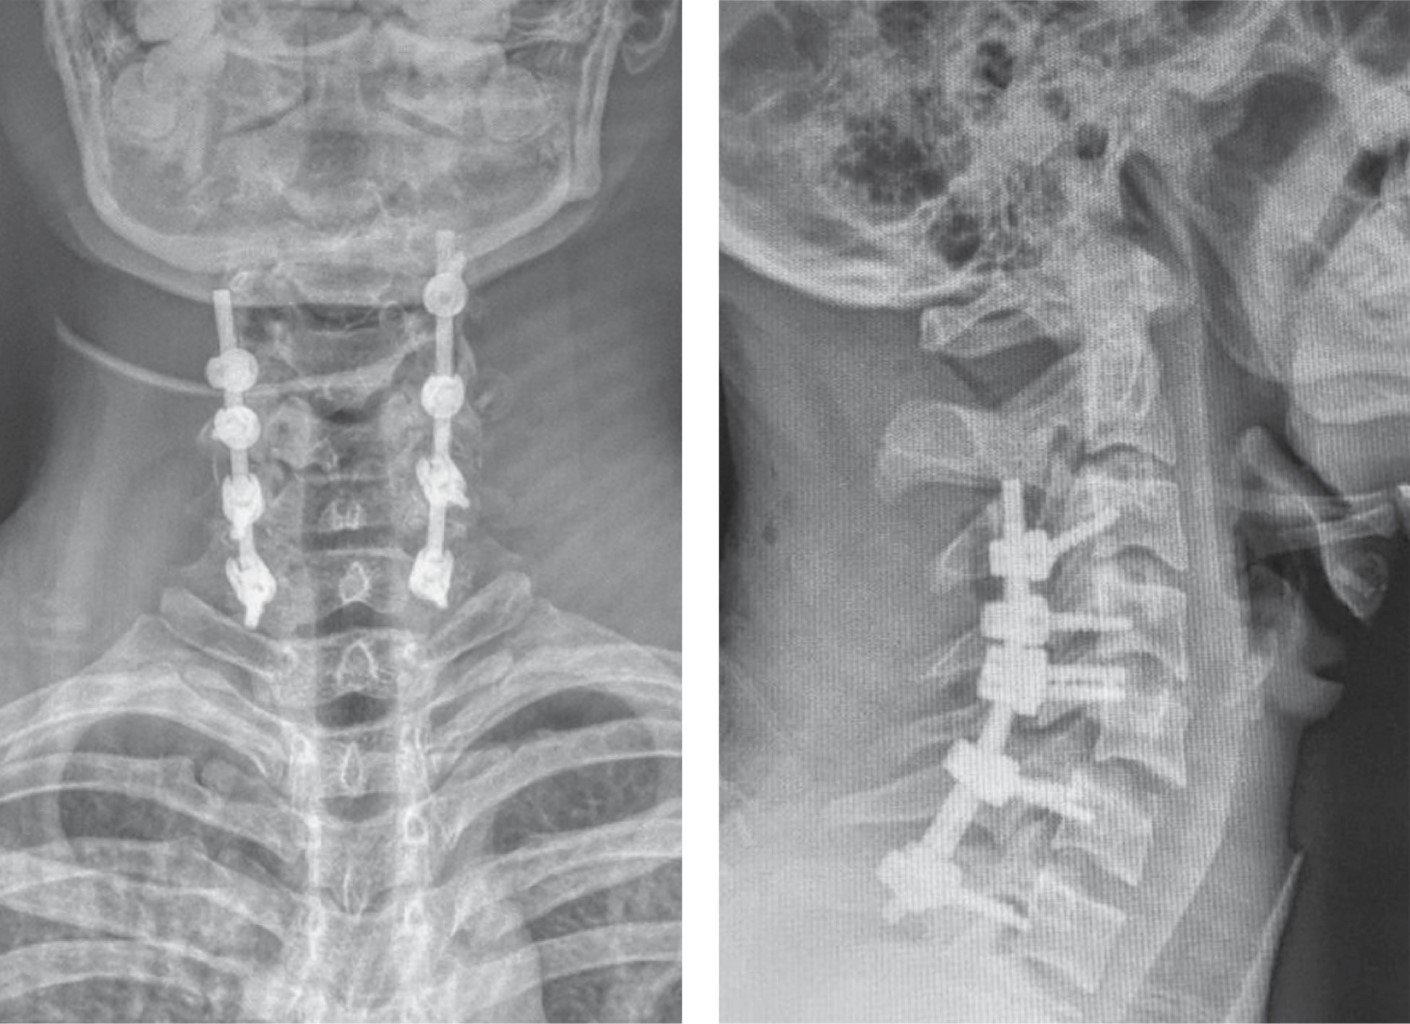

Introducción: la luxación cervical subaxial es una grave lesión, usualmente debido a un trauma de alta energía. El manejo es controvertido, más aún cuando el cuadro neurológico está intacto. Tener los estudios necesarios para evaluar el método de reducción (abierto o cerrado), así como la mejor opción de abordaje (anterior, posterior o 360°). Presentación de caso: paciente masculino de 19 años con historia de accidente de motocicleta, asistido en Hospital Regional de Petén, Guatemala. El examen neurológico evidencia función sensitiva y motora completa, radiológicamente (rayos X y tomografía) con fractura luxación C5-C6. Paciente fue inmovilizado y transferido a nuestro centro hospitalario. Al ingreso, se le realiza tracción esquelética con peso de 12 kg, con obtención de reducción parcial. Posteriormente, se realizó una instrumentación mediante abordaje posterior de C3-C7, el paciente evolucionó con adecuada función neurológica. Conclusión: el manejo de las luxaciones subaxiales sigue siendo controversial, especialmente en pacientes con un cuadro neurológico estable. La evaluación clínica adquiere un papel fundamental en centros hospitalarios sin acceso a resonancia magnética, ya que la reducción cerrada puede ser una opción efectiva siempre que se acompañe de una vigilancia neurológica continua. Asimismo, el abordaje posterior permite favorecer la cicatrización de los elementos posteriores y facilita la evaluación futura para un posible retiro del material, considerando la preservación de los discos intervertebrales.

Figura 2